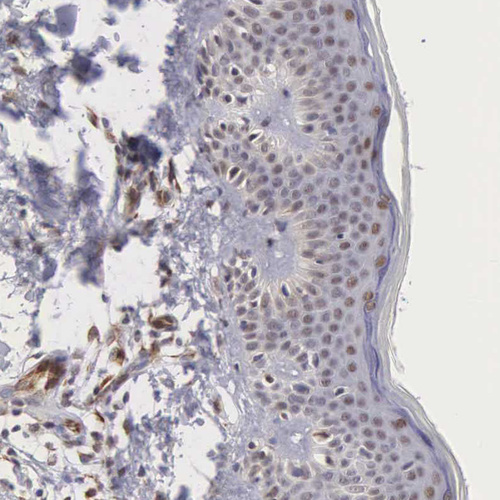

Immunohistochemical staining of human testis shows strong nuclear positivity in cells in seminiferous ducts.